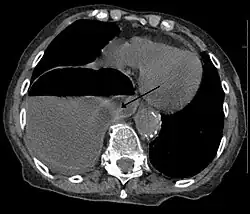

Hérnia diafragmática é um defeito ou buraco no diafragma que permite que o conteúdo abdominal chegue à cavidade torácica. O tratamento é usualmente cirúrgico.

O diagnóstico pode ser feito por tomografia computadorizada ou raio-x. Diagnosis can be made by either CT or Xray.